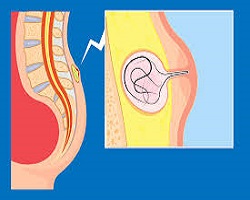

| Хемороиди или фиброваскуларни јастучићи аналног канала су део нормалне анатомске структуре и сматра се да су веома битни за одржавање континенције. Постоје два типа хемороида у односу на локализацију: спољашњи (у доњем делу аналног канала, испод зупчасте линије) и унутрашњи (у горњем делу аналног канала, изнад зупчасте линије). |

| Бенигна хиперплазија простате (БХП) представља немалигно увећање простате, које се често јавља код мушкараца старијих од 50 година. Ово стање се сматра физиолошким и обично није проблематично све док не доведе до симптома који утичу на квалитет живота пацијента. |